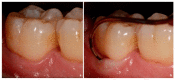

Various classification systems have been proposed to describe furcation lesions and Glickman's classification for many years seems to have been the most widely utilized in the sole clinical diagnosis with no reference to the prognostic value of the lesion itself. This article reviews the previous classification systems and proposes a new method to classify furcation lesions based on the position of the gingival margin and its relationship with the furcation area (clinically exposed/non-exposed furcation area) providing significant aid for a better understanding of furcation involvements and increases the prognostic value of treatments in the long term.